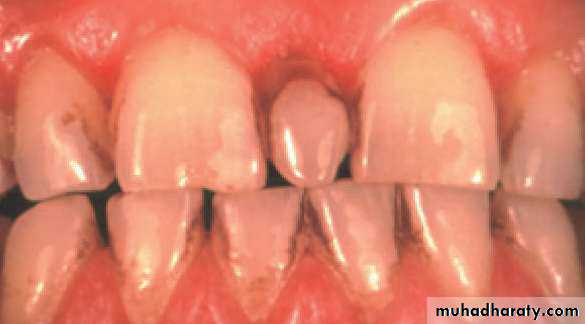

• Mesiodens :When they occur between the maxillary central incisors.

Mesiodens

If they erupt, they can cause malalignment of the normal dentition.